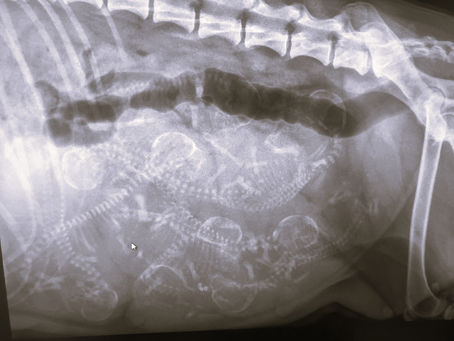

Røntgen tatt av Ona i dag

I dag, ni dager før termin, tok vi røntgen av Ona og det blir tydeligvis et bra stort kull. Vanskelig å i eksakt antall, men mest...

18. mars 2022